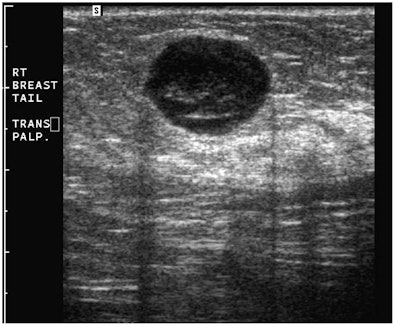

"A simple, yet powerful application of PDUS is differentiating between a rounded, markedly hypoechoic tumor and a [thickened] cyst with low-level internal echoes," he said. "The detection of the smallest vessel within the lesion automatically excludes a cyst -- or any other fluid collection -- and confirms a neoplasm. This very simple yet very useful application of PDUS is still underused."

| Images are of a circumscribed round pseudocystic mass. Above, grayscale US shows a cystic appearing mass with some low-level internal echoes. Below, PDUS performed with only minimal pressure applied through the probe shows internal vascularity, thereby excluding a fluid-filled lesion and confirming a tissular mass. Fine-needle aspiration readily confirmed a metastasis from a uterine leiomyosarcoma treated six years previously. All images courtesy of Dr. Bruno Fornage. |